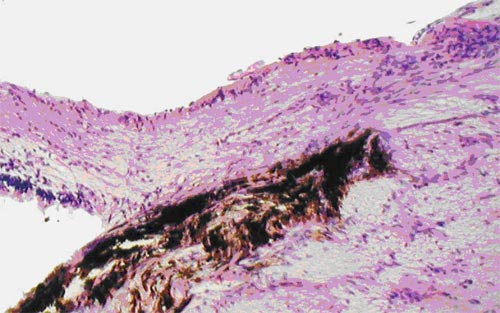

В группе кроликов № 2 с экспериментальной глаукомой атрофия аксонов и экскавация диска зрительного нерва сочеталась с пролиферацией астроцитов. В преламинарной (хориоидальной) части зрительного нерва при окраске по методу Шпильмейера наблюдалось неравномерное утолщение осевых цилиндров, связанное с натеками нейроплазмы, их очаговая вакуолизация. Фрагментации волокон до выхода аксонов из глаза не наблюдалось. В ретроламинарной области, в зоне миелинизированных волокон, изменения осевых цилиндров в виде натеков нейроплазмы, вакуолизации были более выражены. Выявлена фрагментация отдельных осевых цилиндров, миелиновые оболочки с проявлениями набухания местами подвергались растворению и деструкции с образованием ситообразных пространств с тканевым детритом, что являлось признаками кавернозной (лакунарной) дистрофии зрительного нерва, описанной при глаукоме [4]. При окраске по методу Ван Гизон наблюдалось разрастание соединительной ткани за счет пролиферации глии вокруг переполненных кровью капилляров с периваскулярным склерозом. При окраске на гликозаминогликаны альциановым синим в ретроламинарной области реакция была отрицательной.

Электронно-микроскопическим исследованием в группе № 2 с АИГ установлено очаговое или тотальное расслоение миелиновых оболочек, формирование вакуолей, которые сдавливали и деформировали набухшие митохондрии, в некоторых митохондриях происходило образование кистозных полостей. Наблюдалось разрежение нейротрубочек и нейрофибрилл, очаговое их разрушение, замещение вакуолями с хлопьевидным содержимым повышенной электронной плотности.